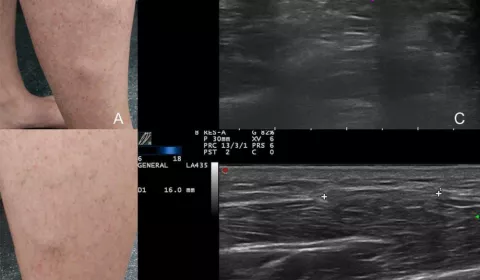

【趣聞】肌肉也會疝氣? 30初頭熱愛跑步的男子進到診間,就指著小腿前側的突起說:「醫生,這個腫起來的小包已經好幾個月了,我只要跑超過一公里就會痛到受不了,這是什麼問題?」 超音波探頭放上小腿前側,立刻看到筋膜有個小缺陷,讓肌肉從這邊被擠出去,也就是「肌肉疝氣」。 肌肉疝氣相對罕見,通常發生在活動量大的族群,或是小腿受到外力撞擊、穿刺傷害後。如症